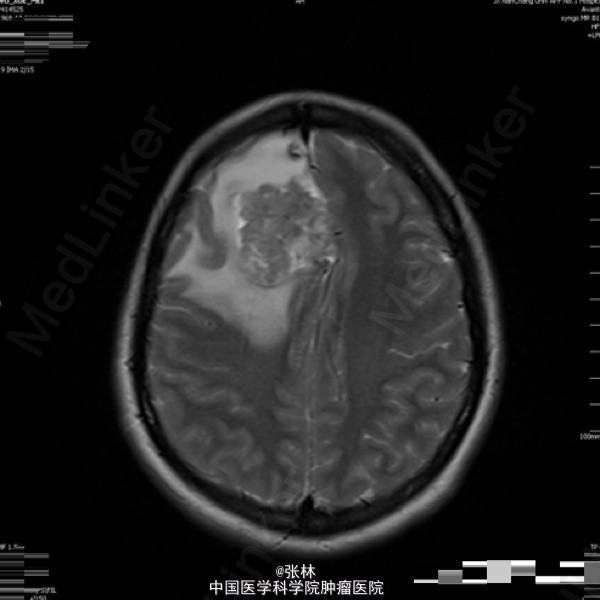

42岁女性,10余天前无明显诱因出现头痛,并呕吐胃内容物,双眼视物模糊。影像学表现:右侧额叶见一不规则形占位性病变,大小约为3.7×4.0×4.5cm,T1WI呈等、低信号,T2WI呈等、高信号,DWI仍呈高信号,周围脑组织少量水肿,增强扫描后病变呈明显强化,边缘水肿无强化。 病理: 镜检:肿瘤细胞弥漫增生,呈乳头状、腺样,细胞核卵圆形,深染。 免疫组化示:GFAP(散在细胞+)、Vimetin(+)、S100(-)、CK(+)、EMA(+)、ki-67(5%+)、CD99(部分+)、CD56(+)、NF(-)、CD34(-)、Hepa(-)、AFP(-)、mammaglobin(-)、RCC(-)、WT-1(-)、CD10(-)、CK7(-)、CK20(-)、Villin(-)、CR(-)、MC(-)、MOC31(-)。及少许脂肪组织,上皮混合组成。 讨论: 室管膜瘤来源于脑室与脊髓中央管的室管膜细胞或脑内白质室管膜细胞巢的中枢神经系统肿瘤。在胶质瘤中占6%,男多于女,多见于儿童及青年,约75%位于幕下,幕上仅占25%。文献报道幕上室管膜瘤75 ~85 %位于脑室外。脑实质内室管膜瘤起源于室管膜细胞嵴,可能是神经管内折叠时形成畸形的结果,好发部位为丘脑,其次为额叶、颞叶、顶叶。实性多见于成人,囊性多见于青少年。 幕上室管膜瘤以头痛、呕吐、嗜睡、厌食及复视等颅高压症状为主,多有局部运动功能障碍和癫痫。